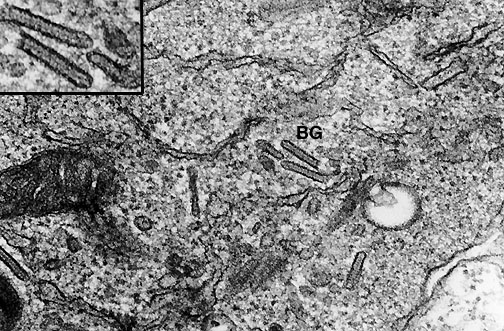

Birbeck granules (BG) (inset shows several at higher magnification) are seen here in a Langerhans cell from a case of histiocytosis X, one of the forms of peculiar neoplastic proliferations known as the Langerhans cell histiocytoses.